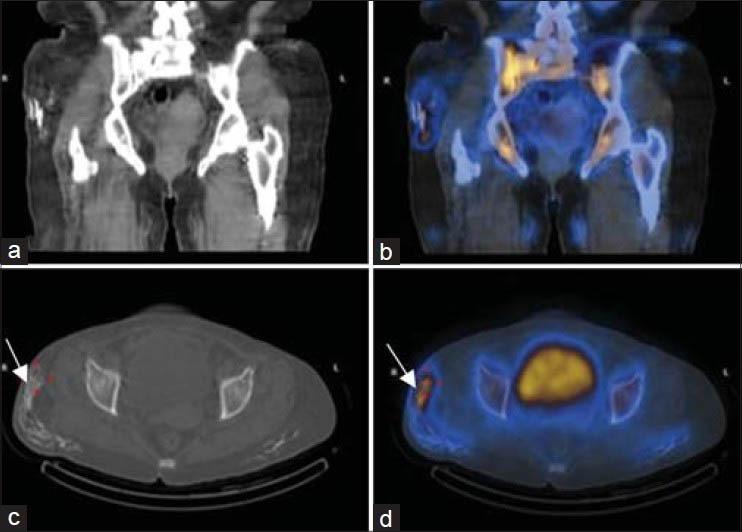

Calcinosis, although frequent in juvenile dermatomyositis is a rare finding in adults. It is more common in later phases of the disease, involving sites under chronic stress and trauma. We present a 52-year-old female patient of dermatomyositis who on single-photon emission computed tomography/computed tomography hybrid images showed exclusive subcutaneous fat calcinosis, also known as calcinosis universalis - a phenomenon that is only rarely reported in adult-onset dermatomyositis.